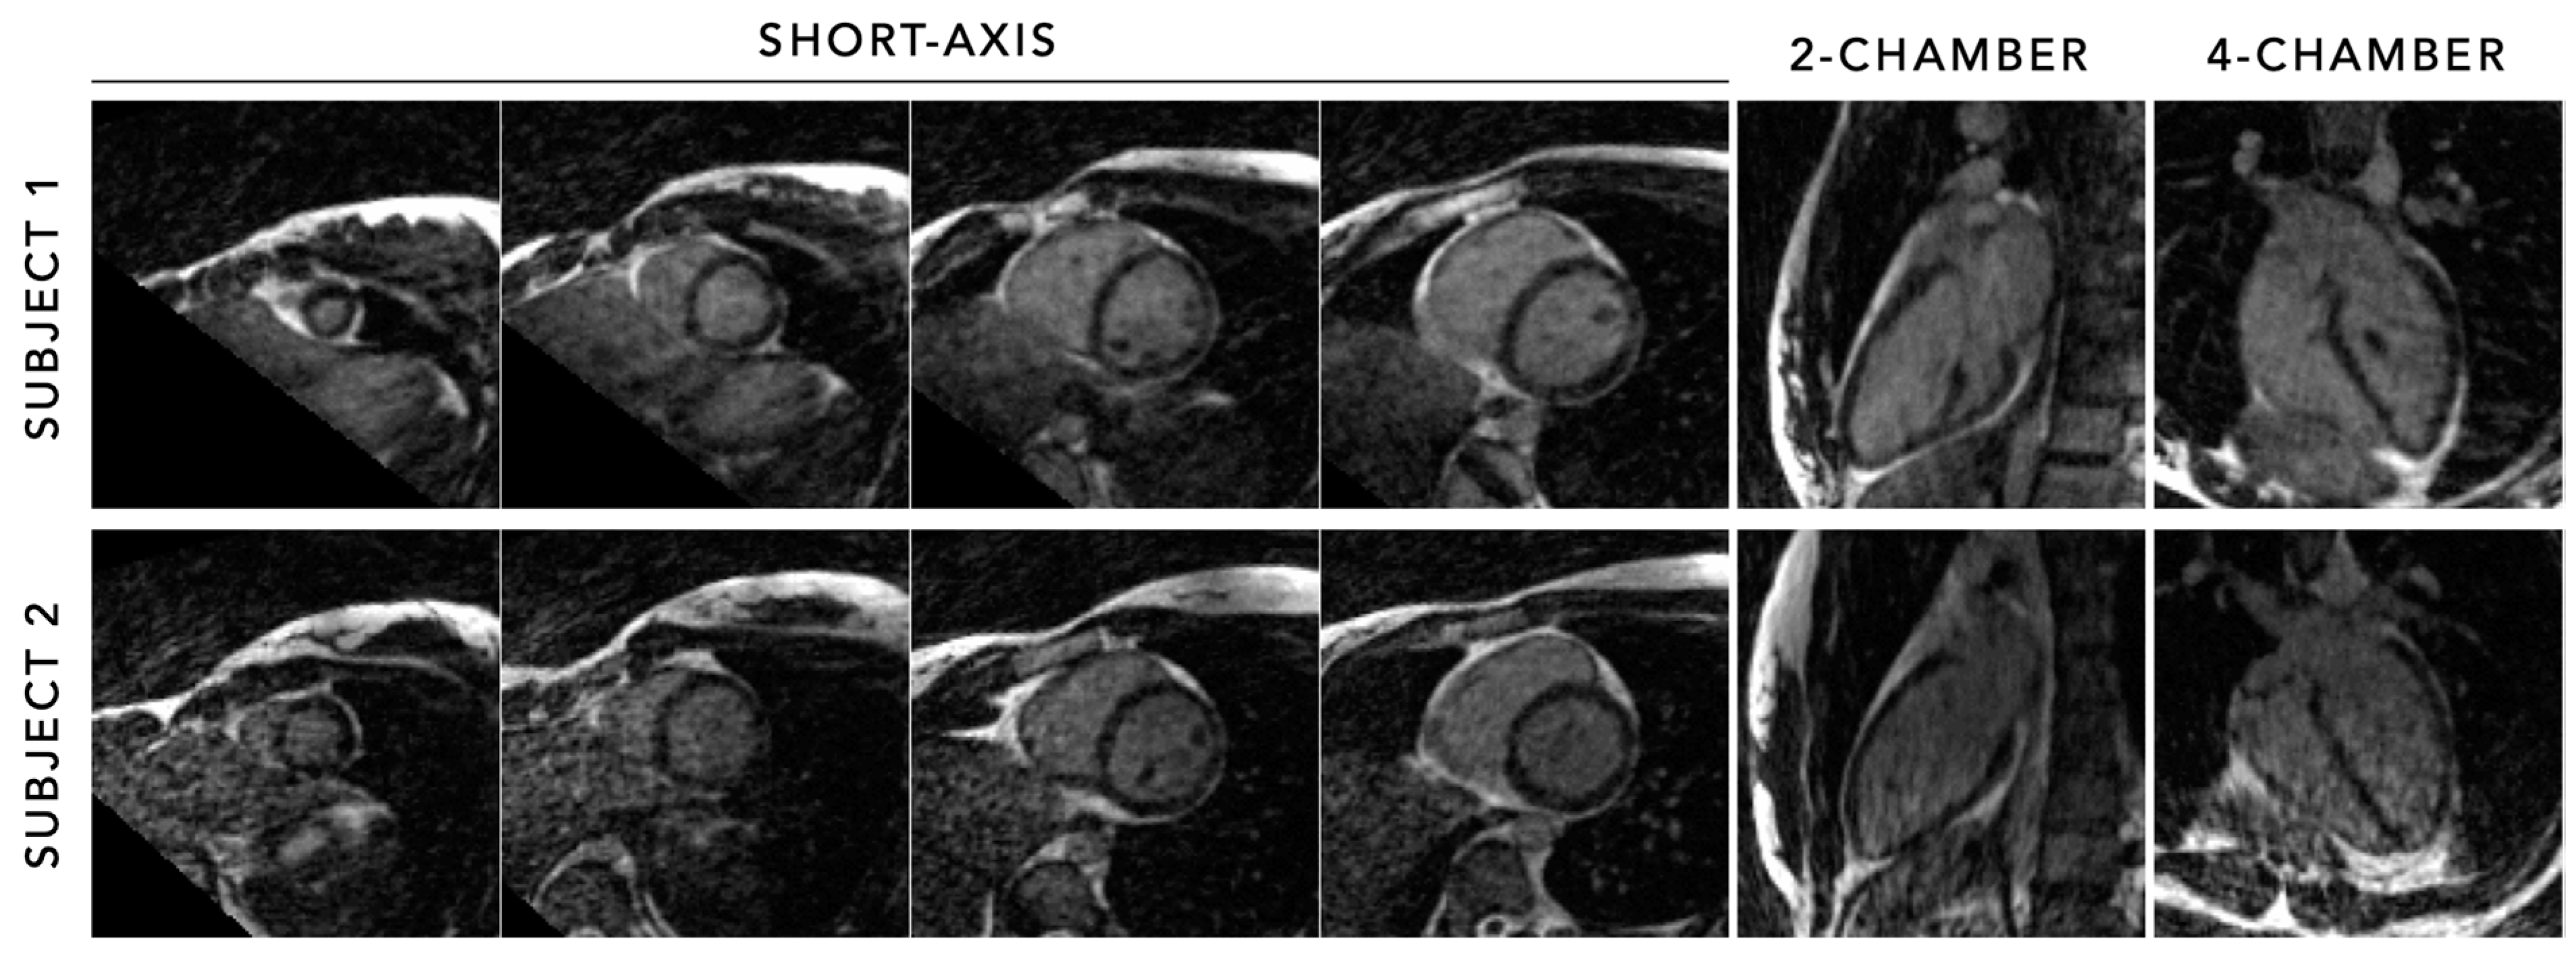

- Roy, C.W.; Di Sopra, L.; Whitehead, K.K.; Piccini, D.; Yerly, J.; Heerfordt, J.; Ghosh, R.M.; Fogel, M.A.; Stuber, M. Free-running cardiac and respiratory motion-resolved 5D whole-heart coronary cardiovascular magnetic resonance angiography in pediatric cardiac patients using ferumoxytol. J. Cardiovasc. Magn. Reson. 2022, 24, 39. [Google Scholar] [CrossRef]